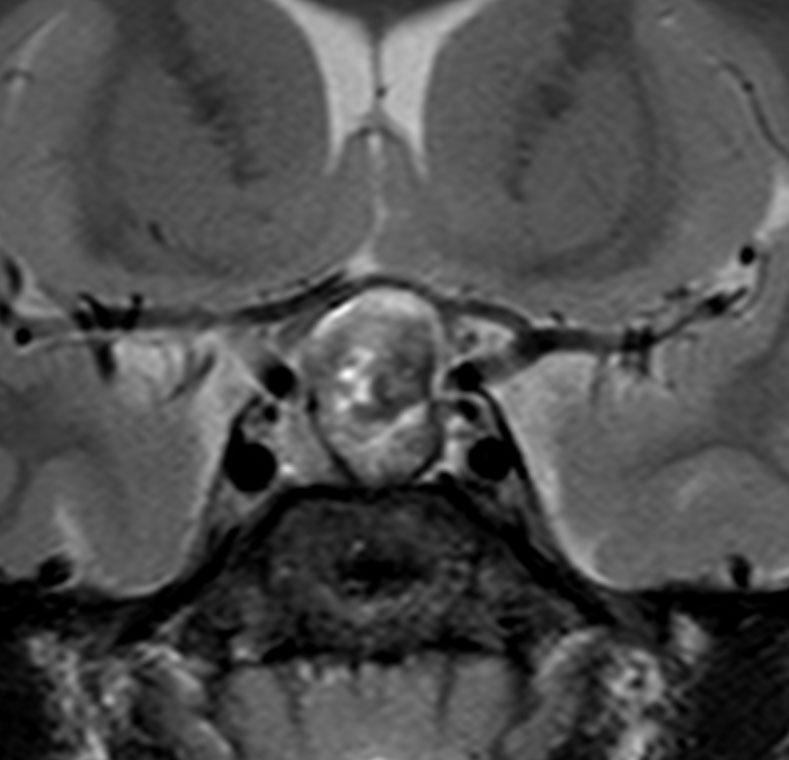

矢印の先に見えるように下垂体は正常の形態です。この画像から灰白隆起の左後方,乳頭体の前方が腫瘍発生母地ということがわかります。尿崩症もなく下垂体機能は正常です。経鼻的な内視鏡手術で腫瘍の大部分を摘出すれば下垂体機能は廃絶します。

とにかく失明を避けるために急いで経蝶形骨洞手術(transsphenoidal-transtuberculum sellae approach)で腫瘍のう胞の減圧をしました(緑の矢印の経路 by 函館中央病院加藤功先生)。その後に前頭開頭で腫瘍を全摘出しました(右側の画像)。尿崩症はでましたが下垂体前葉機能は正常です。

右視力 0.45,左明暗弁の視力が残りました。でももし,経鼻手術をしないでいきなり開頭すればおそらく全盲になっていた例です。